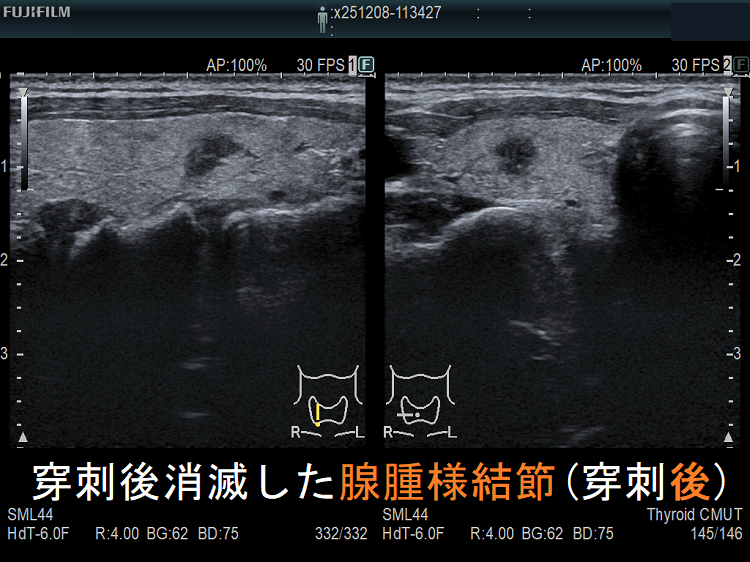

穿刺細胞診後内部融解

ケース①

ケース②

![穿刺後消滅した腺腫様結節(穿刺後) [拡大] 穿刺後消滅した腺腫様結節(穿刺後) [拡大]](../images/basic/basic5/images20251216212323.png)